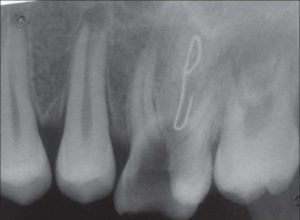

Imbasan X-Ray menunjukkan terdapat imej yang gelap yang menunjukkan kehadiran bendasing di dalam nanah tersebut.

Bengkak tersebut dicucuk dan air nanah di keluarkan. Rupanya terdapat dawai stapler yang tertusuk di celah gigi sehingga ke akar gigi pesakit.